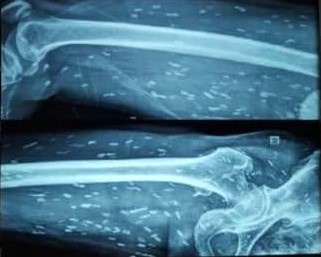

Các khớp khỏe mạnh cho phép chúng ta đi lại, cầm nắm đồ vật và thực hiện các chuyển động một cách dễ dàng, thoải mái. Khi già đi, các vấn đề về khớp có thể xảy ra gây đau, cứng khớp, hạn chế khả năng vận động. Ảnh: Pexels.